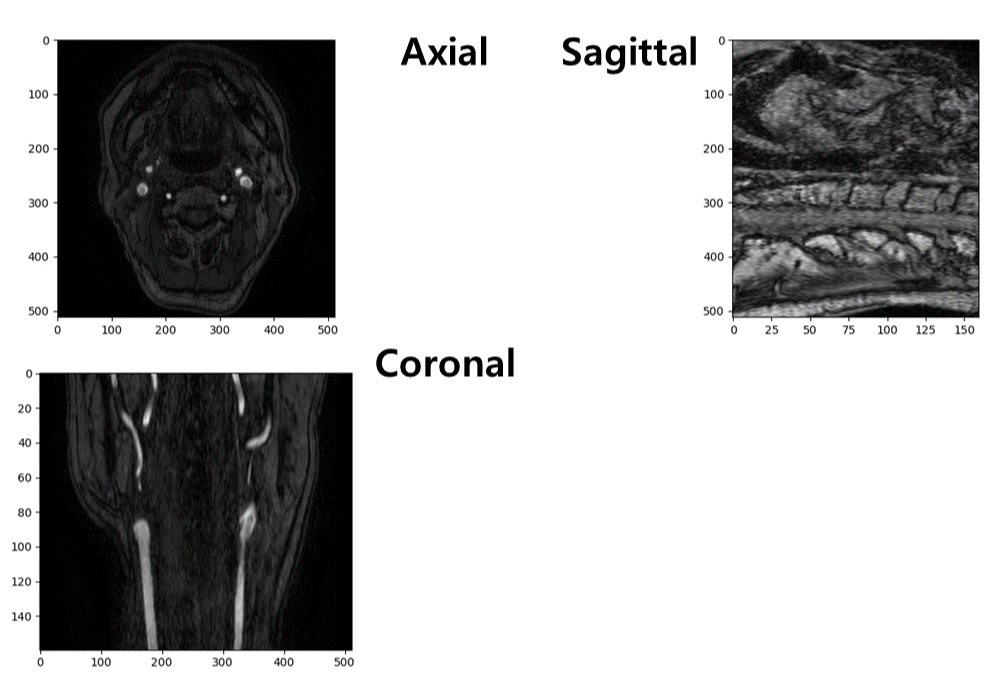

마지막은 3차원으로 구성한 데이터를 시각화하는 부분입니다. Subplot를 통해 하나의 창에 다수의 이미지를 시각화할 수 있게 하였고 Img_shape [0], Img_shape [1], Img_shape [2]를 통해 각각의 해부학적 평면의 중간에 위치한 이미지를 시각화할 수 있도록 하였습니다.

다음은 전체 코드의 결과 그림을 나타냅니다.

결과물을 자세히 보면 Radiant보다 늘어나 있거나 회전되어 있는 모습을 볼 수 있습니다. 해당 문제는 다음 글에서 다루어 보겠습니다.